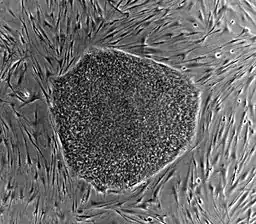

Robert N. Klein II, motivated by the suffering of family members from autoimmune diseases, launched a citizen initiative known as Proposition 71 in 2004, which created a state-funded center for stem cell research - the California Institute for Regenerative Medicine (CIRM).[4] Based in San Francisco, the CIRM is responsible for with making grants and loans to stem cell research initiatives focused on developing treatment methods and completing research for clinical trials.[5] Proposition 71 was approved by 59% of California voters and authorized $3 billion in bonds to fund the CIRM in addition to creating a Governing Board of 29 members as an Independent Citizens' Oversight Committee (ICOC).[6] By 2020, $2.75 billion of the original $3 billion has been used or earmarked for funding of basic research, infrastructure, education, and clinical translational studies.[7] For this reason, Klein spearheaded this initiative to authorize an additional $5.5 billion in bonds for the CIRM to support additional grants and operations under Proposition 14.[8] Research areas of focus at CIRM include stem cell based research to mitigate or cure serious illness and chronic diseases such as cancer, heart disease, kidney disease, respiratory illnesses including COVID-19, diabetes, cancer, HIV/AIDs, paralysis, blindness, and more. A dedicated $1.5 billion under funding from Proposition 14 will be dedicated to research of diseases specific to the central nervous system and brain, including cancer, autism, dementia, Parkinson's and Alzheimers' disease.[9]